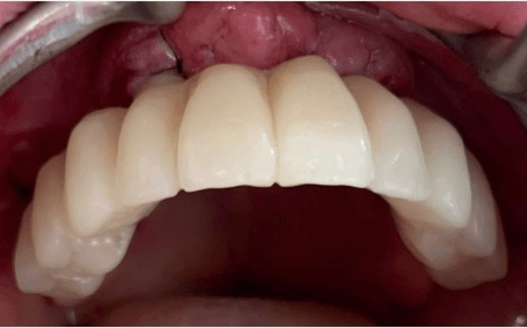

Paciente con edentulismo completo y reabsorción avanzada en maxilar superior.

Rechaza opción removible.

Se planifica rehabilitación completa con 4 implantes Zygoma.

Se colocan 4 implantes Zygoma según planificación 3D guiada bajo sedación IV, Carga inmediata a las 24 horas.

La paciente fue rehabilitada de forma definitiva a los tres de meses en su clínica origen.